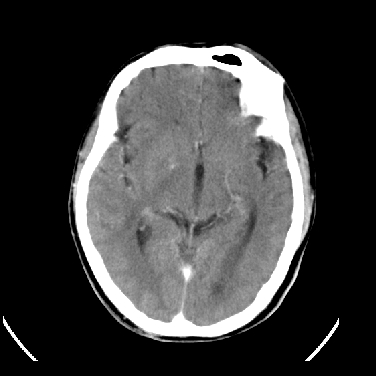

男,45岁,左侧肢体乏力1周。ex:胸片示:两肺团块状、斑片状密度增高影,其内可见小空洞。支纤镜、经皮肺穿示:干酪样物。

结合病史考虑结核性脑炎脑膜炎,伴脑脓肿形成

考虑右侧顶叶脑脓肿形成。

同意“考虑结核性脑炎脑膜炎,伴脑脓肿形成”的意见,不轻易怀疑肿瘤。

考虑结核性脑炎脑膜炎,伴脑脓肿形成。

考虑右侧顶叶脑脓肿(结核性?)。

结核性脑脓肿可能大

结合病史考虑结核性脑炎脑膜炎,伴脑脓肿形成,囊变转移瘤不除外